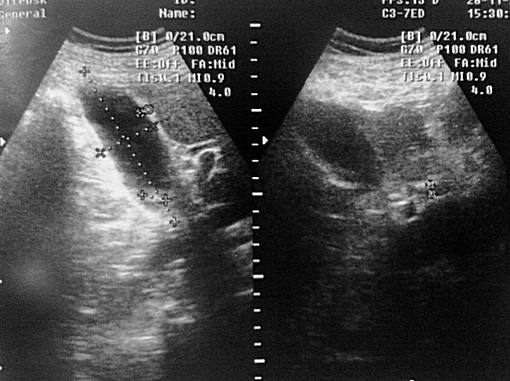

УЗИ ЖКБ.Острый гангренозный холецистит.

Мужчина 68лет, жалобы на боли в правом подреберье:

Через 2 дня боли уменьшились, но появилась Т38,4:

Желчный пузырь с неравномерно утолщённой стенкой на всём протяжении . Дифференцировка слоёв отсутствует ...

Диагноз подтвержден "операционно"...

Кстати нарушение целостности видно и здесь: Послеоперационный диагноз (списала с истории болезни): ЖКБ.Острый калькулезный гангренозный холецистит. Перфорация желчного пузыря. Местный перитонит.